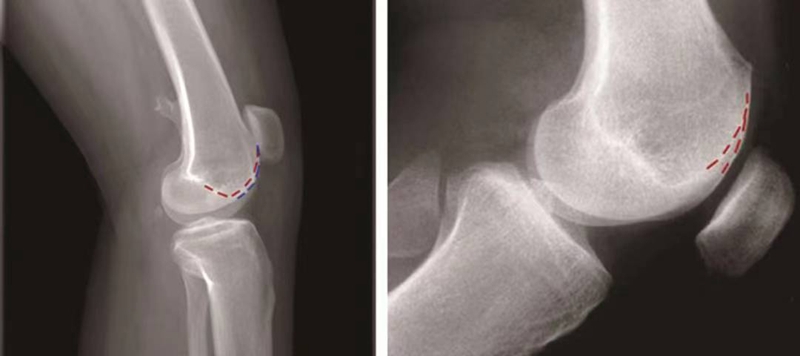

①交叉征:

H.Dejour在1987年介绍了股骨滑车发育不良在膝关节标准侧位X线片的特殊表现,描述了交叉征(crossing sign)。在股骨滑车发育不良的膝关节标准侧位像上,股骨滑车沟基底线会与股骨外髁的轮廓线相交叉,即为交叉征(图11),意味着股骨滑车发育平坦。

图11 交叉征

②突起征:

H.Dejour在1996年提出突起征(spur或bump)或滑车近端突起征(supratrochlear spur),是指在膝关节标准侧位像上,股骨滑车沟基底线的最高点位于股骨前方皮质延长线的前方(图12)。这种征象的实质是股骨滑车近端的整体抬高。在膝关节屈曲早期,髌骨必须越过滑车近端的突起才能进入股骨滑车,因此,容易出现髌骨向外脱位。如果突起征>5mm即为异常,意味着股骨滑车基底高于股骨外髁的轮廓。

图12 突起征

③双轨征(或称为双线征):

是指在膝关节标准侧位像上,代表股骨内外侧滑车的两条线分开,呈双轨样(图13)。它的出现提示股骨内侧滑车发育低平,导致它的前缘出现晚于外侧滑车。

图13 双轨征

(3)股骨滑车发育不良的分型:

1996年,D.Dejour和B.Le Coultre提出了更准确的股骨滑车发育不良的四种分型(图14):

图14 股骨滑车发育异常分型 A型:交叉征;B型:交叉征+突起征;C型:交叉征+双线征;D型:交叉征+突起征+双线征